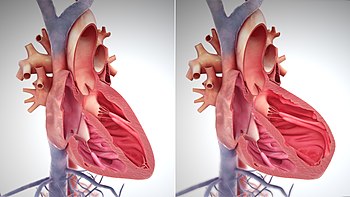

More accurate classification of heart failure type is made by measuring ejection fraction, or the proportion of blood pumped out of the heart during a single contraction.[34] Ejection fraction is given as a percentage with the normal range being between 50 and 75%.[34] The two types are:

1) Heart failure due to reduced ejection fraction (HFrEF). Synonyms no longer recommended are "heart failure due to left ventricular systolic dysfunction" and "systolic heart failure". HFrEF is associated with an ejection fraction of less than 40%.[35]

2) Heart failure with preserved ejection fraction (HFpEF). Synonyms no longer recommended include "diastolic heart failure" and "heart failure with normal ejection fraction."[4][18] HFpEF occurs when the left ventricle contracts normally during systole, but the ventricle is stiff and does not relax normally during diastole, which impairs filling.[4]

Echocardiography is commonly used to support a clinical diagnosis of heart failure. This modality uses ultrasound to determine the stroke volume (SV, the amount of blood in the heart that exits the ventricles with each beat), the end-diastolic volume (EDV, the total amount of blood at the end of diastole), and the SV in proportion to the EDV, a value known as the ejection fraction (EF). In pediatrics, the shortening fraction is the preferred measure of systolic function. Normally, the EF should be between 50% and 70%; in systolic heart failure, it drops below 40%. Echocardiography can also identify valvular heart disease and assess the state of the pericardium (the connective tissue sac surrounding the heart). Echocardiography may also aid in deciding what treatments will help the person, such as medication, insertion of an implantable cardioverter-defibrillator or cardiac resynchronization therapy. Echocardiography can also help determine if acute myocardial ischemia is the precipitating cause, and may manifest as regional wall motion abnormalities on echo.

Ultrasound showing severe systolic heart failure[37]